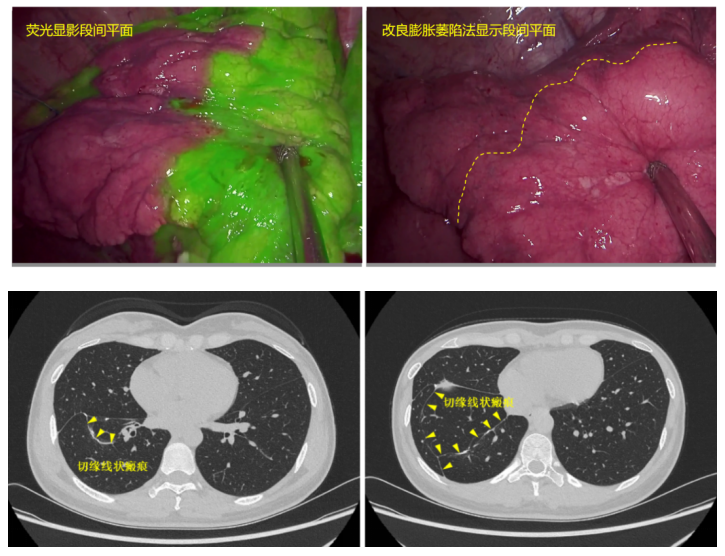

针对上述难题,在刘伦旭教授、蒲强教授的指导下,治疗团队最终设计了分别经肺裂及肺下韧带的“双入路”手术路径、经前外基底段之间行“肺劈裂”的手术策略、采用荧光显影及改良膨胀萎陷“双显示法”的综合手术方案,逐一突破各个手术难点。

2023年3月,刘成武副主任医师主刀顺利完成手术。手术切口仅约4cm,手术持续169分钟,术中出血量仅约20毫升。术后病理证实右肺下叶为浸润性腺癌。目前,患者术后已近两年,复查未见明显肿瘤复发转移征象,CT显示肺切缘仅有线样瘢痕,未见明显肺不张,肺功能指标较术前未见显著下降,恢复良好。该手术的成功实施,解决了此类手术中央部位肺段结构暴露问题以及段间平面二次显示困难的问题,为联合肺段、肺亚段甚至次亚段手术提供了创新手术方式。